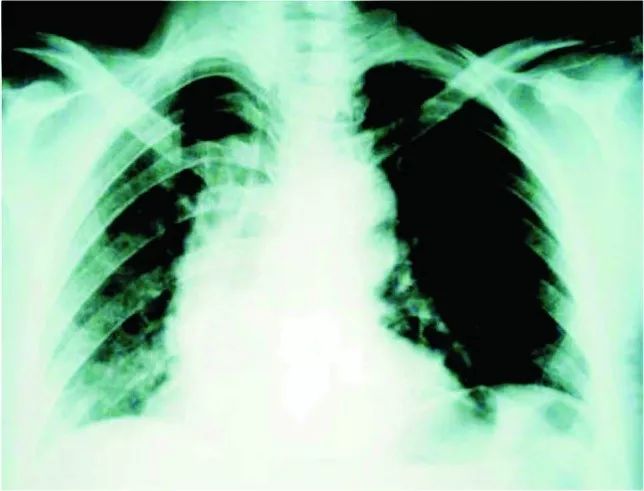

心电图提示:窦性心律,非特异性ST段改变。心肌酶、TnI水平均为正常,D-二聚体升高(13.60 ug/mL),其他实验室检查未见明显异常。急诊医生考虑胸痛原因不太可能是ACS,进行了胸片(图1)及CT检查(图2)。

图1 胸片提示纵膈轻度增宽